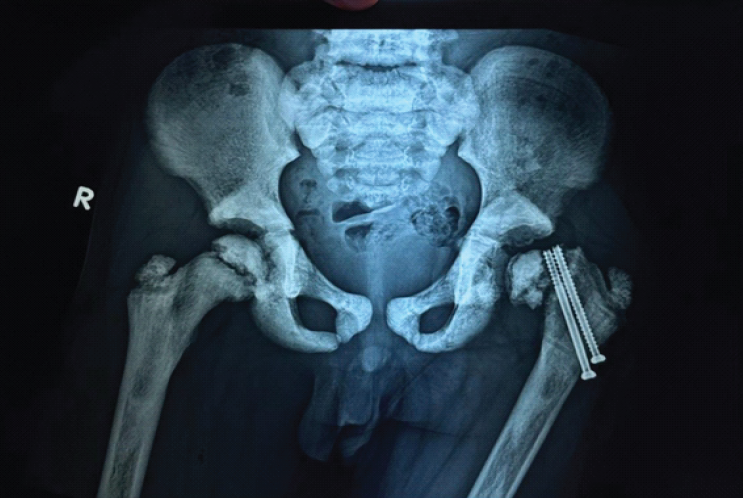

Postoperatively, a hip spica cast was applied for 7 weeks. After removal of the hip spica cast, gradual physiotherapy and progressive weight-bearing were initiated under clinical supervision. Follow-up radiographs after cast removal showed satisfactory fracture healing (Fig. 3).

Figure 3: Radiograph at 7-Weeks follow-up after Hip Spica Cast removal showing progressing fracture union without evidence of avascular necrosis.

At 3 months, the fracture had united without evidence of avascular necrosis or non-union (Fig. 4), and the child had a painless full range of hip movements. Full weight-bearing ambulation was initiated.

Figure 4: Radiograph at 3-month follow-up showing progressing fracture union without evidence of avascular necrosis.

Seven months postoperatively, the child presented with a painless limp and apparent limb shortening. Radiographs revealed slippage of the capital femoral epiphysis despite fracture union (Fig. 5).

Figure 5: Radiograph at 7-month follow-up demonstrating slippage of the capital femoral epiphysis.

The likely cause was stress concentration at the screw tips adjacent to the physis. Revision fixation was deferred due to the small size of the epiphysis and anticipated poor screw purchase. At 1-year follow-up, radiographs demonstrated progression of epiphyseal slippage with significant limb length discrepancy (Fig. 6), although the child remained painless and ambulatory.

Figure 6: One-year post-operative radiograph showing progression of epiphyseal slip with limb length discrepancy.